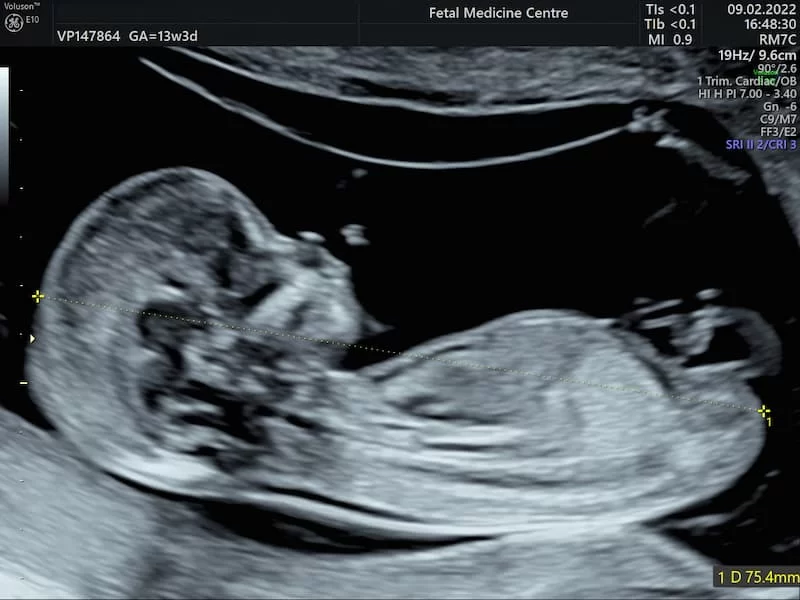

Ultrasonla Cinsiyet Ne Zaman Görülür?

Uzmanlar, bebeğin cinsiyetinin genellikle 18-22. haftalar arasında ultrason ile belirlenebileceğini söylüyor. Bu dönemde bebeğin cinsiyet organları gelişimini büyük ölçüde tamamlamış olur ve deneyimli ultrason teknisyenleri ile doktorlar cinsiyeti güvenle tespit edebilir. Ancak bazı durumlarda bebeğin pozisyonu veya anne karnındaki amniyotik sıvı miktarı, cinsiyetin net şekilde görülmesini engelleyebilir.